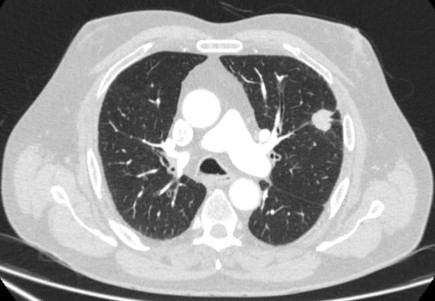

Computed tomography (CT) showing a right upper lobe spiculated solitary nodule within emphysema, in a current smoker with previous asbestos exposure. Note the visible pleural plaque on the left side. Resection histology revealed adenocarcinoma of the lung

From the collection of Dr George Tsaknis, MD, PhD, FRCP(London), MRQA, MAcadMEd, PGCert; used with permission